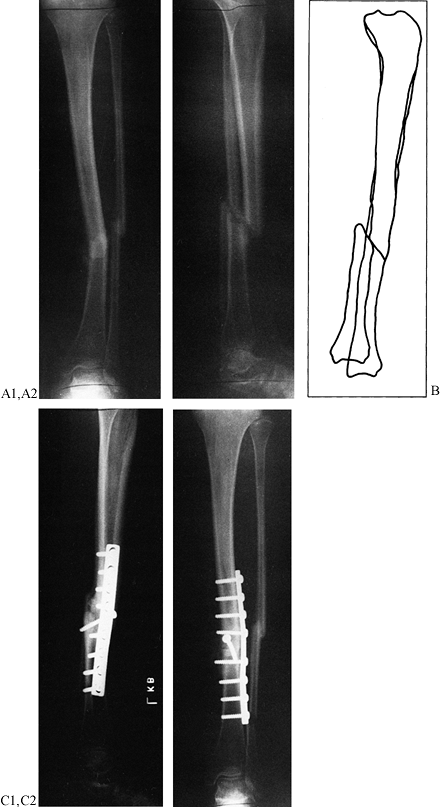

Figure 26.5.

Weber and Cech’s classification of pseudarthrosis. These are the dysvascular, or nonvital, nonunions, in which lack of blood supply, a gap, or another factor limits their ability to heal without biological intervention. A: Dystrophic (torsion wedge with butterfly). B: Necrotic (comminuted fragments). C: Defect (gap). D: Atrophic. (From Weber BG, Cech O. Pseudarthrosis. Bern: Hans Huber, 1976.) |

characterized two nonunions occurring in comminuted diaphyseal

fractures as dystrophic or torsion wedge nonunions with a butterfly

fragment (Fig. 26.5A), and necrotic (Fig. 26.5B)

due to comminuted fragments. In both, there is a devascularized

butterfly fragment, which in the first instance heals to one side of

the fracture and then is partially revascularized. The opposite side

then has a vascularized main fragment abutting a necrotic surface on a

comminuted fragment. The intervening gap is usually filled with fibrous

tissue. In the necrotic nonunion, the healing process fails on both

sides of the comminuted fragment, which produces a devitalized gap.

Both of these nonunions require efforts to induce revascularization of

the devascularized areas, as well as good mechanical stability for

revascularization, and bone grafting to bridge the fracture site.